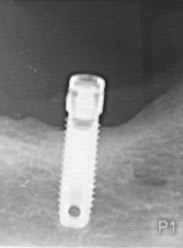

auriez-vous un idée de la marque de cet implant posé il y a plus de vingt ans.

Steri-oss

https://osseosource.com/steri-oss-original-sd-3-25-/p-1114.html

Composants prothétiques pour ainsi dire introuvables maintenant…..désolé mais songe plutôt à déposer…..